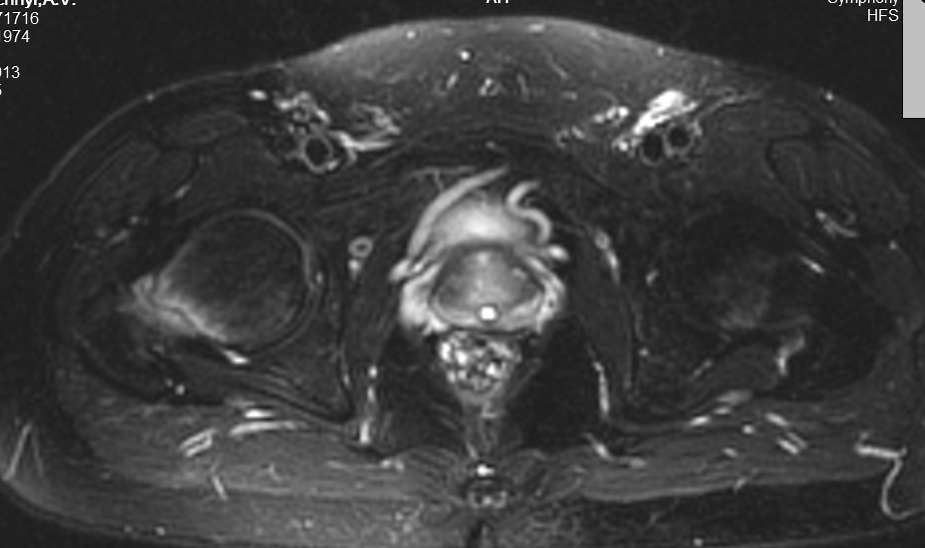

Двухсторонняя патология указывает на стрессовый перелом шейки. По характеру стрессовые переломы разделяются на тензионный в верхнем отделе у пожилых и компрессионнный в медиальной стороне у молодых.

Встречается обычно у бегунов или у активных молодых. МРТ более информативна, чем остальные исследования. Профилактическая перкутанная фиксация винтами поможет уйти от болезненного состояния.

Во вложении похожий случай. Пациентка 50 лет решила подготовиться к любительскому марафону и в течение 2 месяцев бегала 2-3 раза в неделю по нескольку километров. Без предыдущего опыта. Обошлось без операции. Только что вернулась с катания на горных лыжах (через 2 месяца после первичного приема и выполнения МРТ): боли не беспокоят, на консультацию пришла по другому поводу, на компьютерных томограммах изменений нет (поэтому не выкладываю).

сегодня прооперировали - по 3 винта с каждой стороны,о дальнейшей судьбе пациента постараюсь информировать.